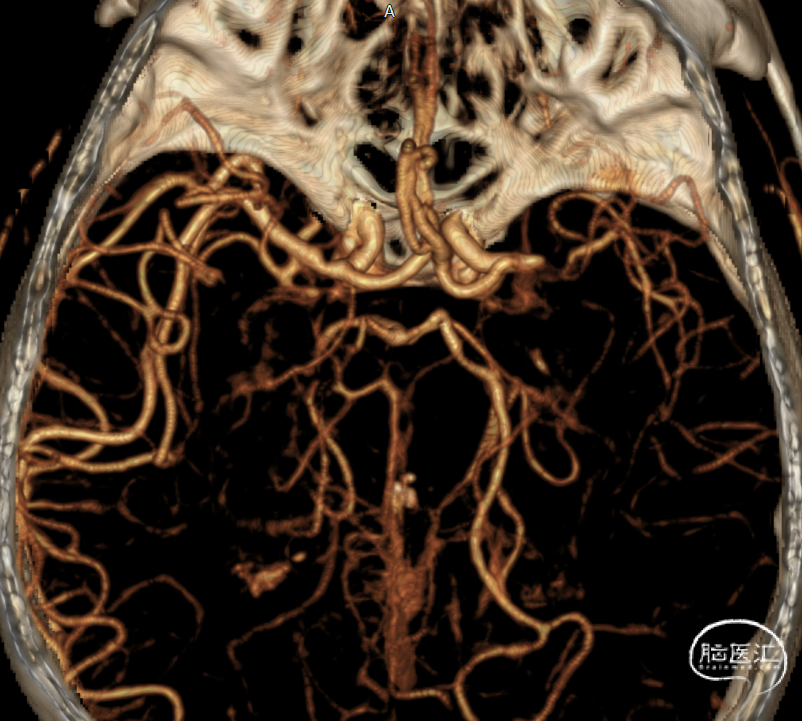

➢术前CTA

4.CTA、MRI、DSA证实右侧大脑中M1闭塞,闭塞长度<1cm。